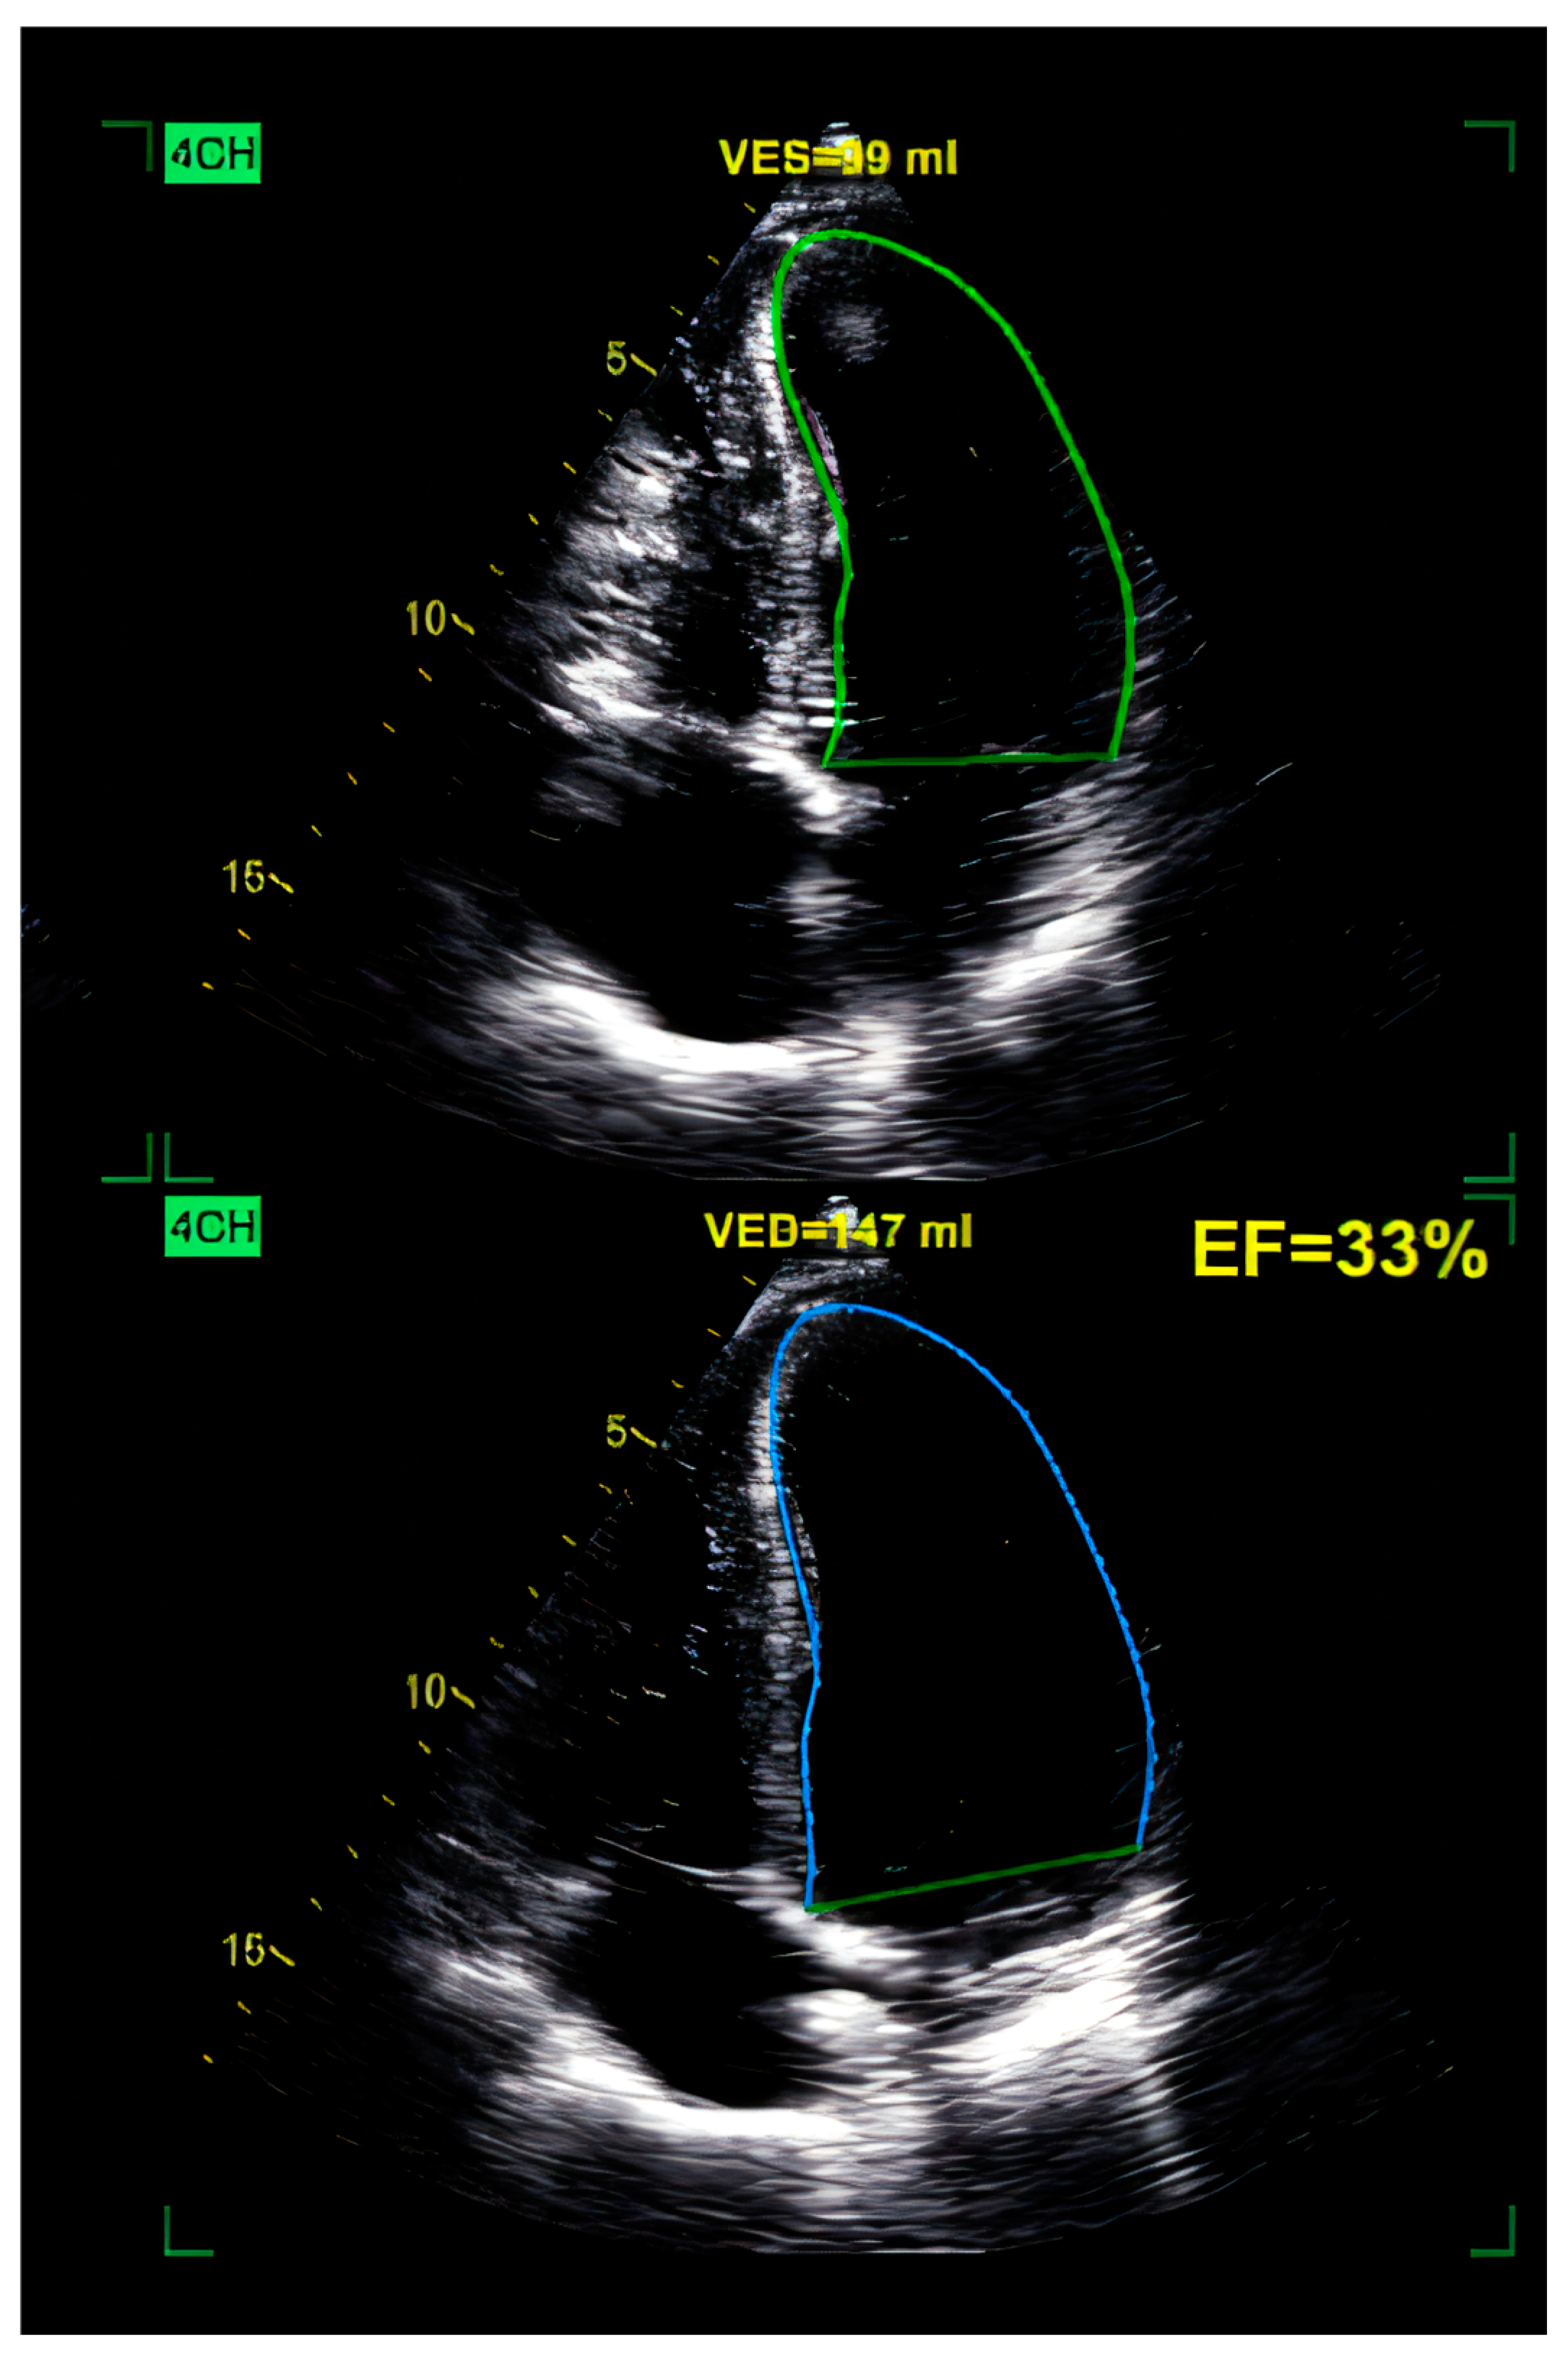

10.3.1. Echocardiography